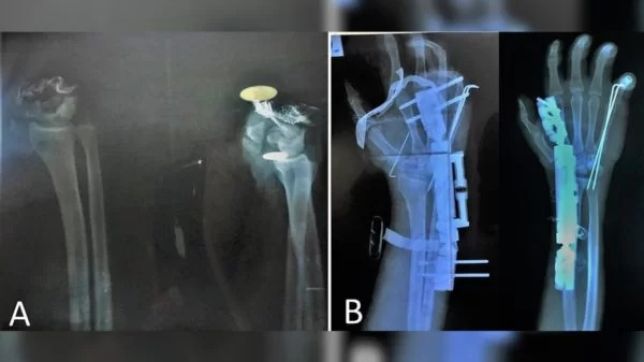

Depois de ter a mão decepada com um cutelo por assaltantes, um rapaz de 20 anos na Síria foi levado rapidamente à emergência de um hospital e, após 10 horas de cirurgia, os médicos conseguiram reimplantar o membro.

O caso foi relatado na revista científica International Journal of Surgery Case Reports em 11 de agosto. Os médicos do hospital Al-Razi contam que o paciente foi levado ao pronto-socorro uma hora depois de ter a mão esquerda cortada. Ela estava envolvida em um pano.

A cirurgia de reimplante foi realizada com anestesia geral e durou 10 horas. “É um procedimento complexo, que exige equipe médica multidisciplinar e equipamentos adequados para a microcirurgia”, aponta a equipe. Eles explicaram ainda que a operação só foi possível pela rapidez com que o rapaz procurou ajuda médica.

O objetivo da cirurgia era reintegrar o jovem à sociedade com as habilidades da mão plenamente restauradas, “o que foi quase bem-sucedido”. O paciente recebeu alta hospitalar sete dias após a operação e foi acompanhado regularmente por dois anos e sete meses.

Para o tratamento de recuperação, o paciente precisou tomar remédios, trocar diariamente de curativos e, depois de certo tempo, iniciar a fisioterapia. Os médicos monitoram periodicamente a capacidade vascular, a união óssea e a recuperação nervosa.

Em uma escala de zero a cinco, a capacidade extensão dos dedos do jovem ao final do tratamento atingiu a nota quatro, assim como a extensão do punho. A capacidade de flexão dos dedos e do punho atingiu nota máxima na mesma escala. “Porém, observamos atrofia nos pequenos músculos da mão: os tenares, hipotenares, interósseos e lumbricais”, destaca o documento.